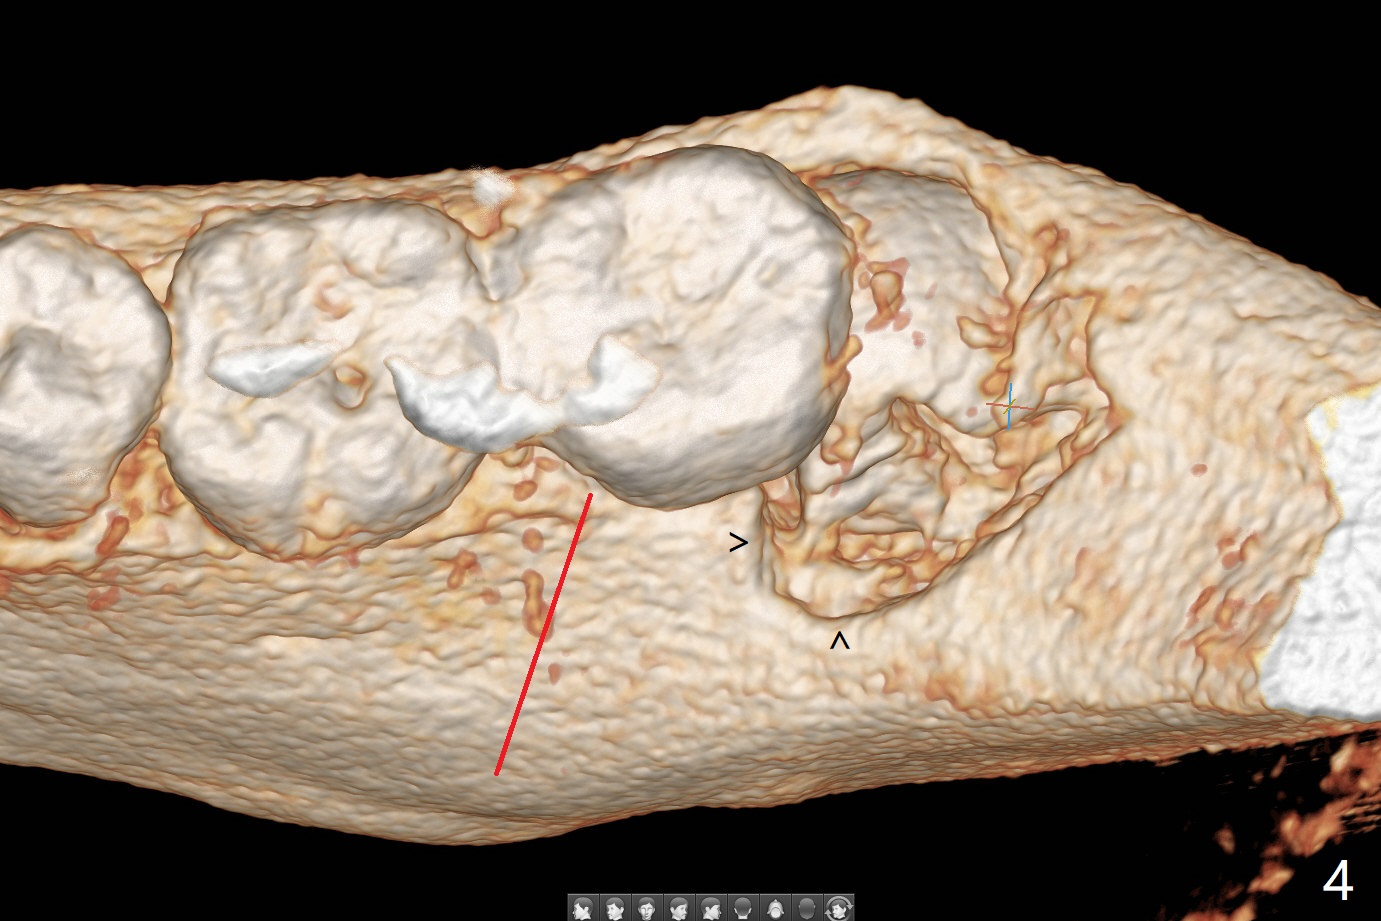

A 27-year-old woman (nervous) is going to return for #16 and 17 extraction (Fig.1). Offer sedative (Valium) if she cannot overcome fear. Take PAs for #17 and 32 to confirm Buccal Impaction, which dictates position of the accessory incision to reduce loss of bone graft in case of wound dehiscence. Place Collagen Plug (1/2 piece) in the apical portion of the sockets of the lower 3rd molars, while Augma and Osteogen Plug (1 piece) in the coronal half of #17 and 32, respectively. Place additional Collagen Plug for the remaining socket if needed before 4-0 PGA suturing as the 2nd step to decrease the chance of losing bone cement. Preop PA shows that the tooth #17 seems to be mesial (Fig.2 arrow). The accessory incision is placed mesiobuccal of the tooth #18 (Fig.4 red oblique line, Fig.6) so that it is not overlying the bony defect (Fig.4 arrowheads). Since the access to the impacted tooth is limited, small field of CT is taken (Fig.3,4), which shows the root is yet to be exposed (Fig.3 R). After tooth removal, Collagen plug is placed in the apex of the socket for hemostasis (Fig.5 C), while Bond Apatite coronal for bone regrowth (A). There is no dehiscence 11 days postop (Fig.7), although the patient complains of pain in the jaw and the temporomandibular region. The anterior portion of the external oblique ridge forms 1 year 7 months postop (Fig.8).